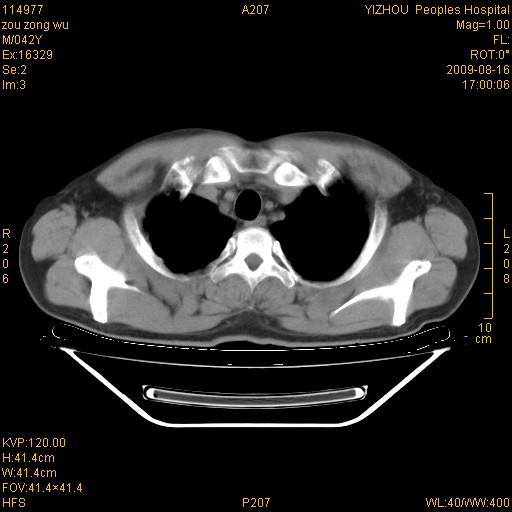

以下是引用zjzjr在2009-8-17 10:42:00的发言:[br]右侧间质性肺炎伴纤维化,右肺下叶肺囊肿伴感染(不除外外伤后引起),右肺野及胸壁软组织\\肝内见多发斑点状,中枪了吧.右侧胸膜肥厚\\粘连.